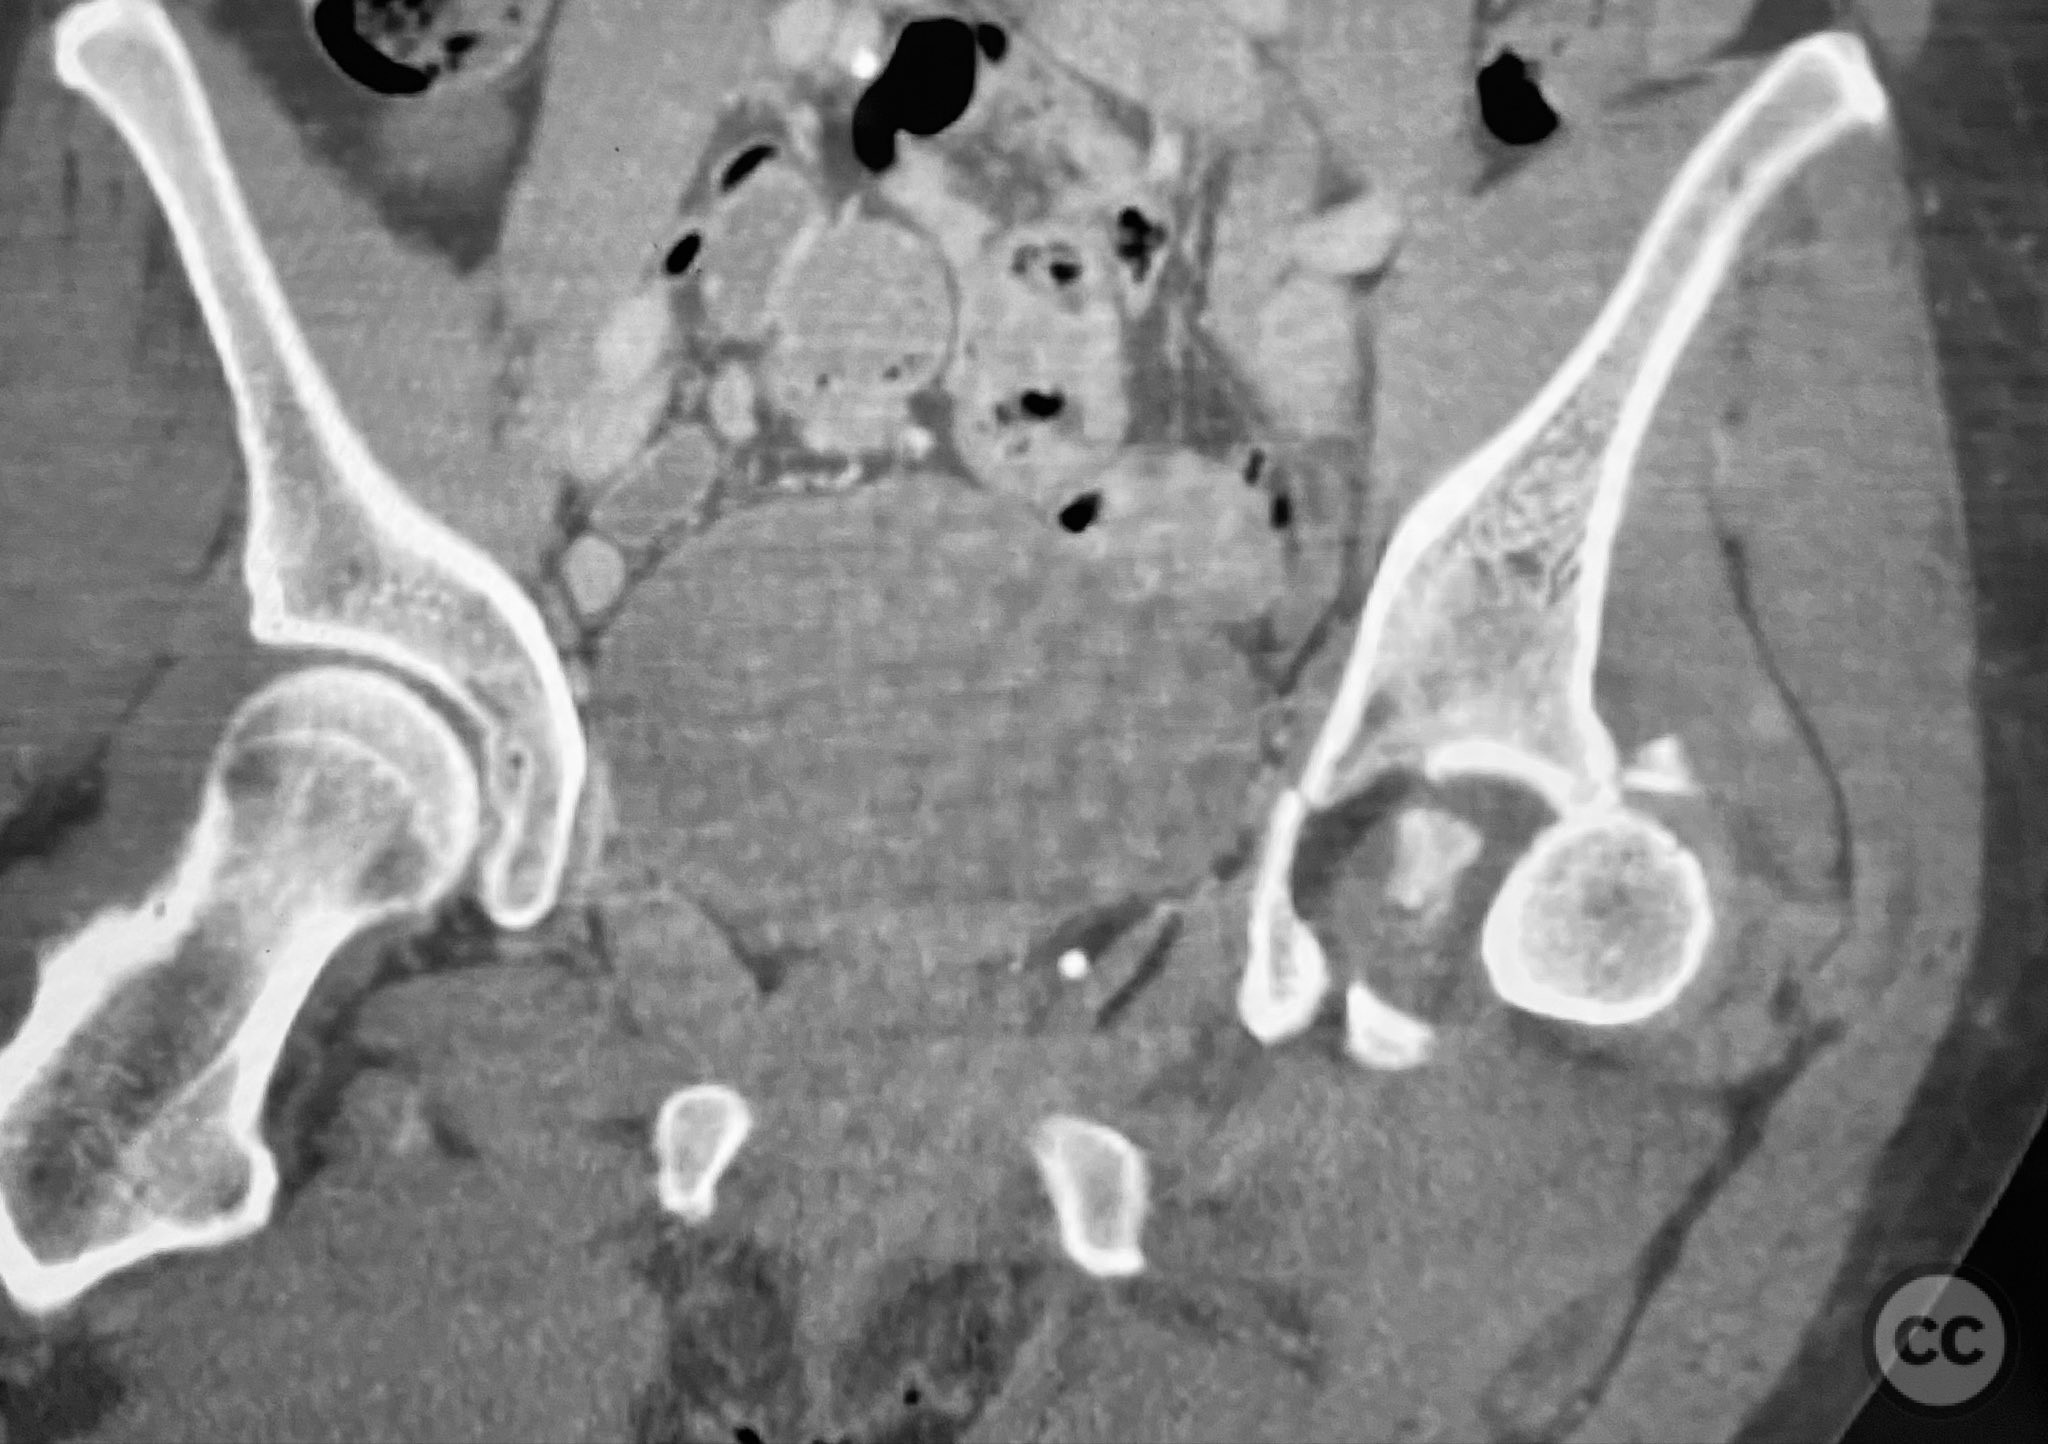

Clinical and radiological findings:  A patient sustained a posterior wall acetabular fracture-dislocation, characterized by comminution of the posterior wall, impaction of fragments into the posterior column region, and intra-articular loose fragments within the fossa acetabuli. Sagittal imaging demonstrated femoral head impalement on the intact wall, raising concern for potential irreducibility. Coronal and axial CT images revealed acetabular and femoral head impactions, peripheral wall comminution, incomplete fracture extension at the acetabular notch and quadrilateral surface, and an articular fragment within the joint. Surface renderings confirmed the extent of peripheral wall comminution and impaction. Despite these findings, a closed manipulative reduction was successfully achieved, resulting in a congruent reduction on post-reduction imaging.

Anatomical surgical approach:  A standard Kocher-Langenbeck approach was performed with a longitudinal incision centered over the greater trochanter, extending proximally along the axis of the gluteus maximus and distally along the femoral shaft. The gluteus maximus was split in line with its fibers, and the short external rotators were detached from their femoral insertions and retracted medially to expose the posterior column and wall of the acetabulum. The sciatic nerve was identified and protected throughout. A distractor was applied across the hip joint to facilitate joint distraction and removal of intra-articular fragments. Impacted articular fragments were elevated, and defects were grafted with ground allograft. Posterior wall fragments were anatomically reduced and stabilized with a combination of plates: a lateral reconstruction plate, a standard buttress plate, and a custom spring hook plate fashioned from a third tubular plate with tines contoured to engage the cortical surface of the posterior wall fragment. The central hole of the spring hook plate was filled first to provide spring tension, followed by fixation of the medial hole to secure the implant.